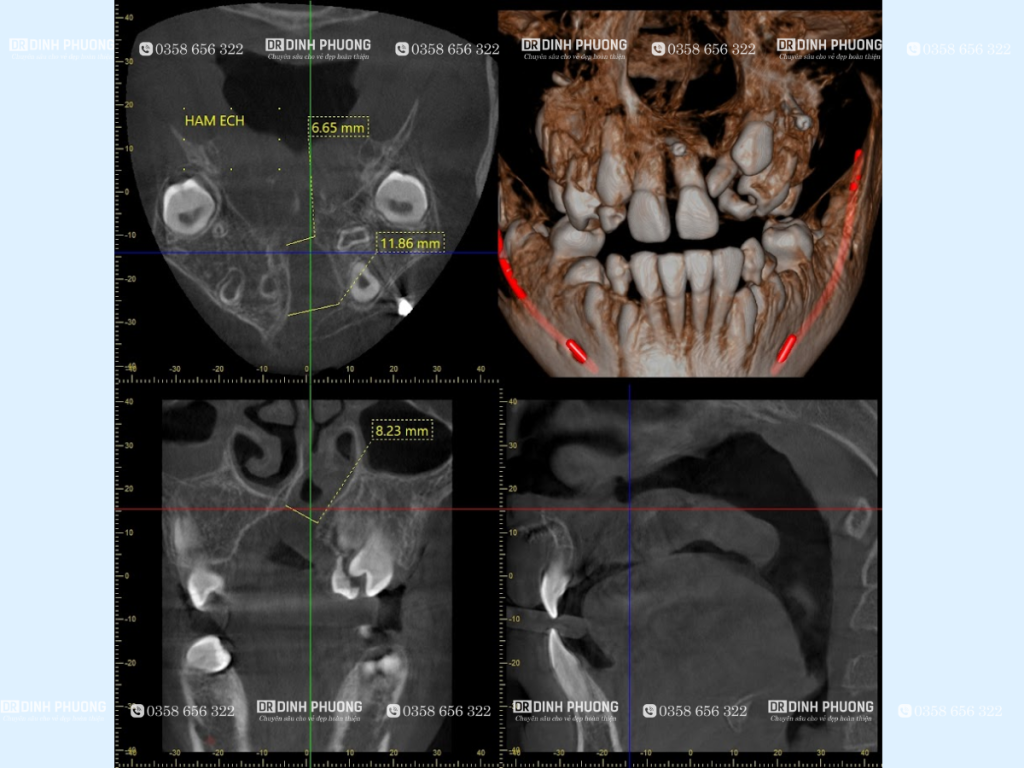

Phim chụp panorama và phim chụp CT Cone beam.

Hình ảnh cho thấy tồn tại khe hở cung răng và vị trí của mầm răng đang di chuyển từ vị trí sàn ổ mắt xuống khe hở, đây là thời điểm thích hợp để tiến hành ghép xương.